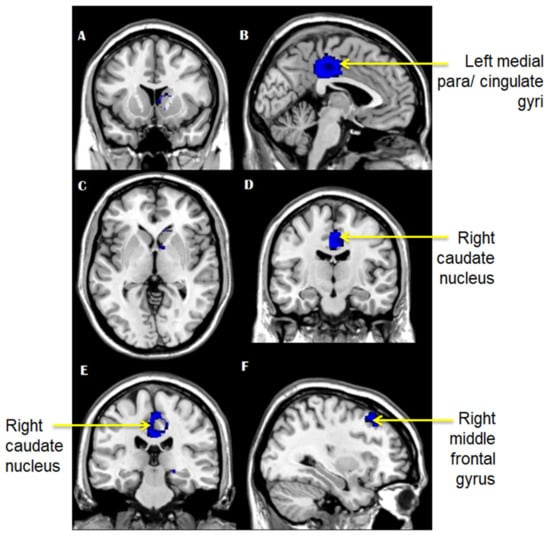

6. GM Volume Increase